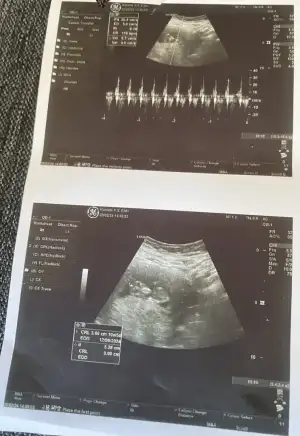

![]()